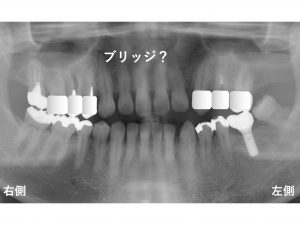

以下は、

上顎左側をブリッジ

上顎右側は、インプラント手術直後です。